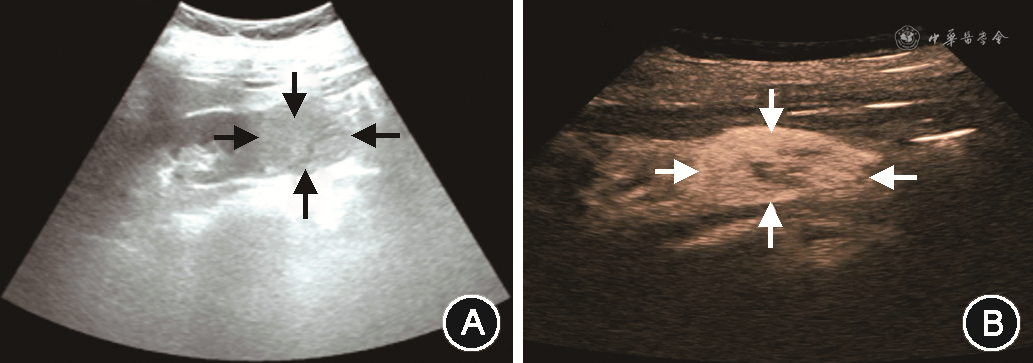

患者女,47岁,因“体检发现右肾占位4 d”于2018年3月2日入住吉林大学中日联谊医院。患者无腰痛,无血尿,一般状态可,基本生命体征正常,否认高血压、糖尿病、冠心病病史,无肿瘤家族史。入院后完善相关辅助检查,常规超声:右肾下极见一高回声团块,大小4.0 cm×3.3 cm,边界欠清晰,向肾外突出(图1A)。超声造影:肿物呈快进、慢退,周边见环状高增强,内部呈不均匀高增强(图1B)。超声提示:考虑肾恶性肿瘤。肾CT检查:平扫见右肾下极稍低密度团块影(图2A),增强扫描病灶呈明显不均匀强化(图2B),提示肾透明细胞癌。结合相关检查,临床诊断为右肾肿瘤,2018年3月13日在腹腔镜下行右肾根治性切除术。术后病理回报:右肾下极多彩样肿物一枚,间质见广泛出血、变性,提示透明细胞乳头状肾细胞癌(clear cell papillary renal cell carcinoma,CCPRCC),病理分期:Ta1,世界卫生组织/国际泌尿病理学会(WHO/ISUP)病理分级:Ⅱ级。免疫组化:细胞角蛋白7(CK7)(+),波形蛋白(Vimentin)(+),碳酸酐酶Ⅸ(CAIX)(+),高分子量角蛋白(34βE12)(+),配对盒基因8抗原(PAX-8)(弱+),细胞增殖核抗原Ki-67(1%+),白细胞分化抗原10(CD10)(-),α-甲酰基辅酶A消旋酶(P504S)(-)。患者术后随访36个月,未见复发及转移。